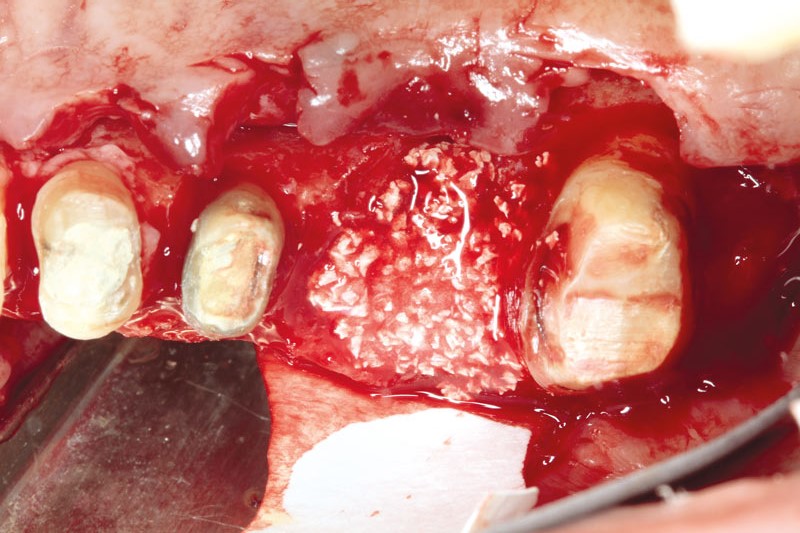

botiss cerabone® & Jason® membrane for GBR - Clinical case by Prof. Dr. Dr. D. Rothamel

Instable bridge situation with abscess formation at tooth #15 after apicoectomy